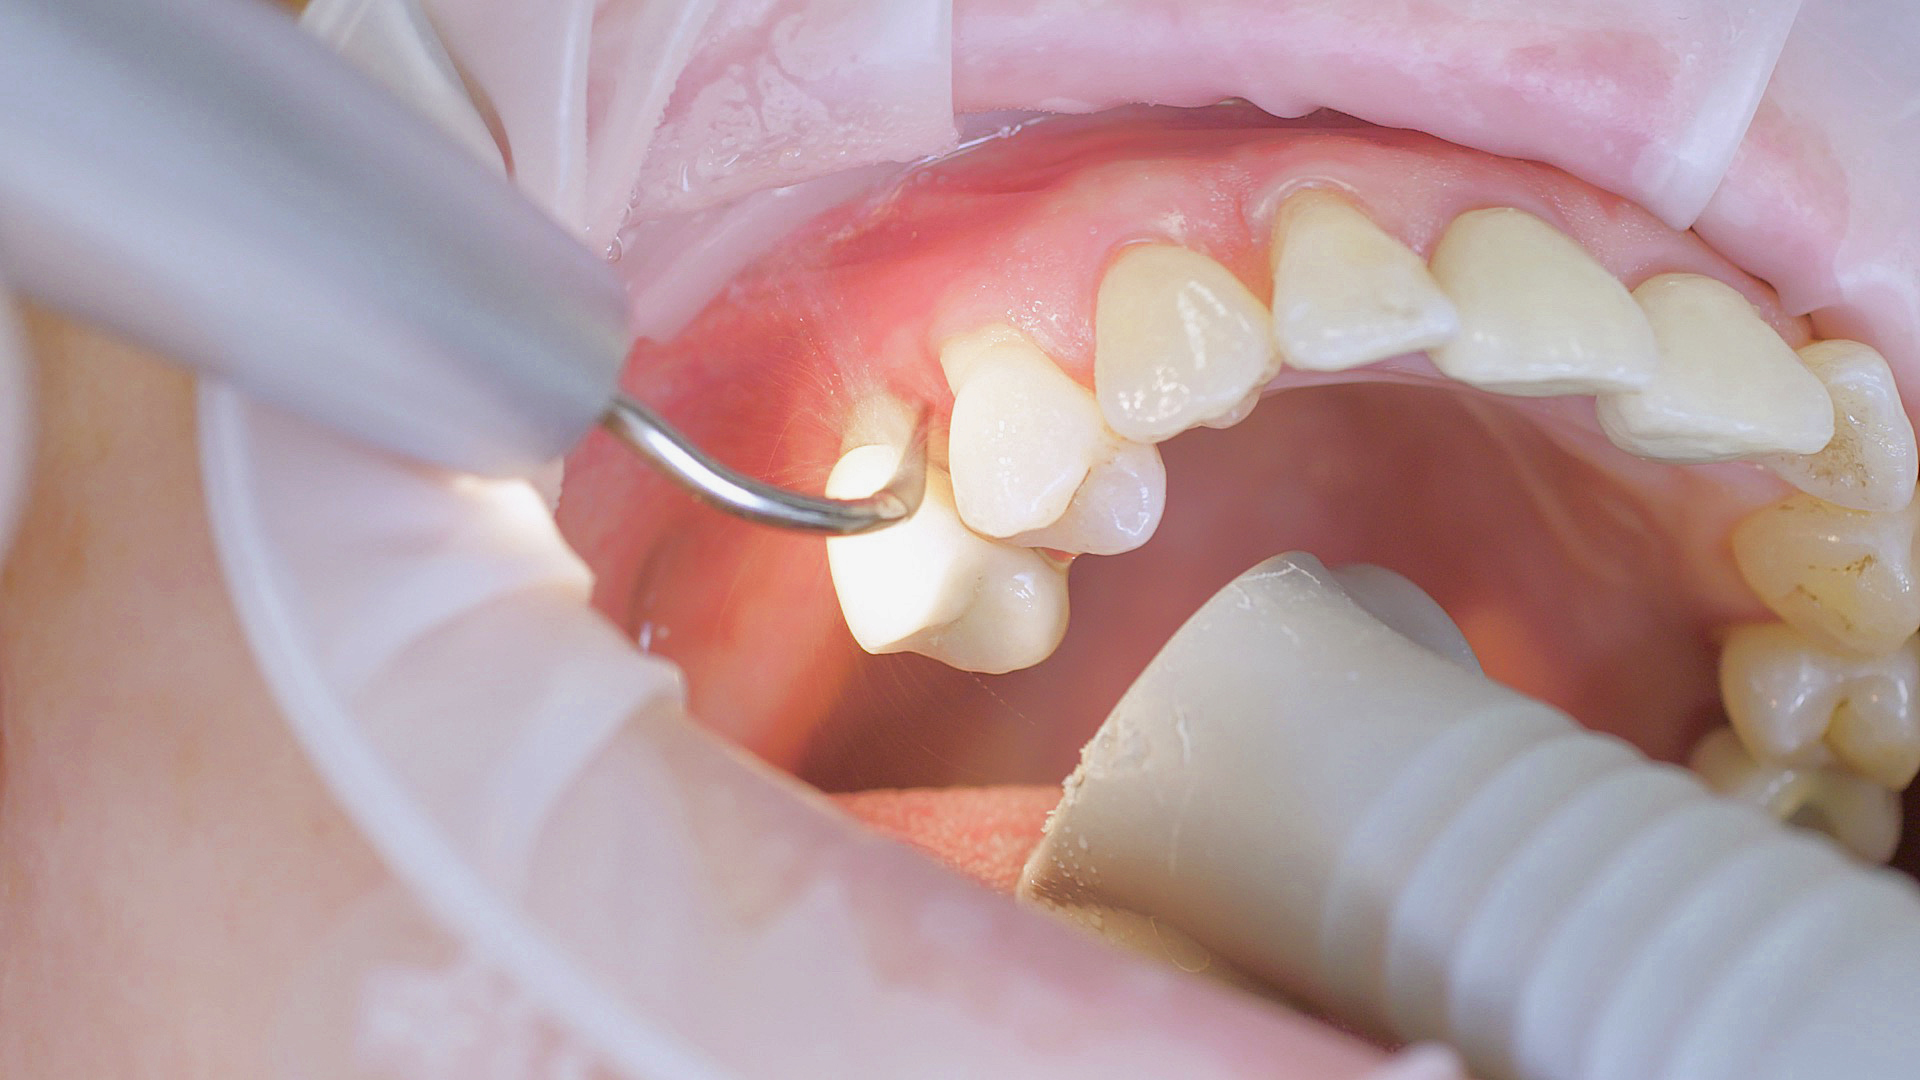

Where necessary, initial periodontal treatment is carried out. First, professional tooth cleaning establishes healthy gingival conditions. In this procedure, calculus (Fig. 1) and biofilm (Fig. 2) are removed as far as the gingival sulcus. In combination with careful instruction on oral hygiene, this gives the patient the basis for long-term freedom from inflammation.15

Rotary cleaning with prophylaxis polishing cups and brushes

Fig. 2: Rotary cleaning with prophylaxis polishing cups and brushes (W&H Proxeo prophylaxis contra-angle handpiece) ensures smooth surfaces on teeth. It enables patients to check biofilm effectively at home.